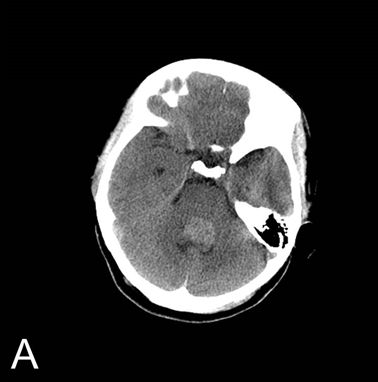

儿童四脑室巨大肿瘤病例分享

指出患儿为第四脑室肿瘤并伴有严重脑积水,病情危重,尽快完善了头部ct

图-6:2012年8月30日头ct脑室分流术后仍脑积水图-7:2012年8月30日入院

术前ct:第四脑室可见类圆形团块状病变,密度稍高,脑沟不明显,脑室扩张